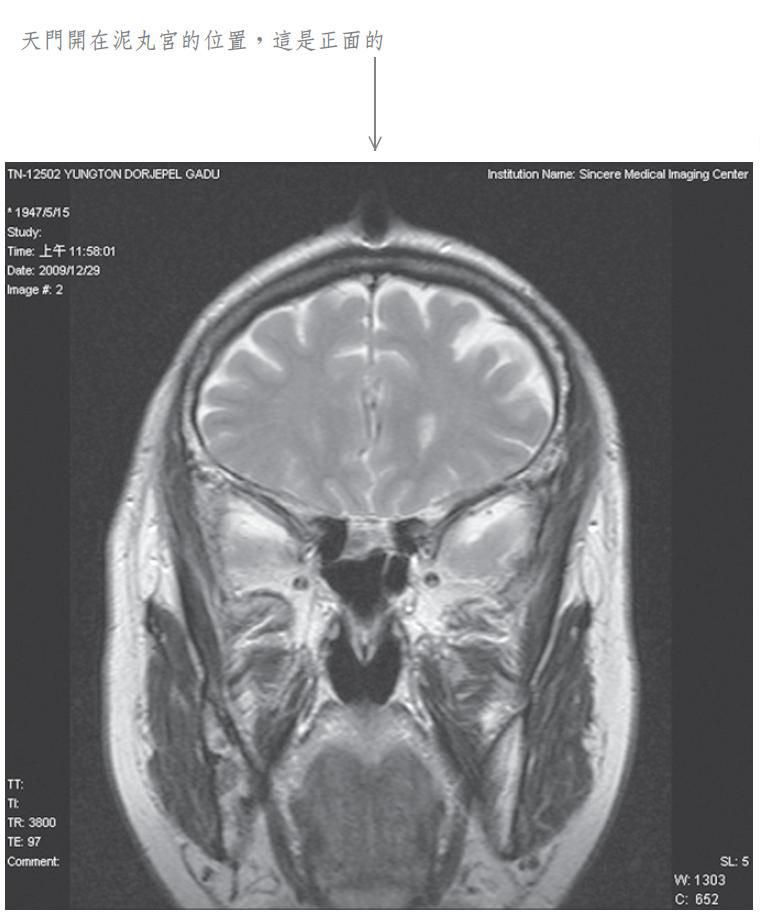

当我将此种修法中发生之觉受禀报佛陀师父时, 佛陀师父又为我传了秘密口诀。经过一段时日, 佛陀师父在公开开示的法音带中,才提到我曾经修法达到化身境的初级,即是素化身的意思。为了让众生明了佛法的伟大,事隔多年之后,我特别于二零零九年十二月廿九日,到中心综合医院安排磁振造影(MRI)头部的摄影检查,结果发现泥丸宫的部位出现一个1.5公分宽深的开口,同时拍下了有一股神识出气冲出头部的实况。负责检查的医生非常惊讶称奇,但无法解释其原因,因而将它归因于非人之所为。我其实非常清楚,我的神识化身本来就是从这里出入的,以下是在医院MRI检查的扫瞄片。